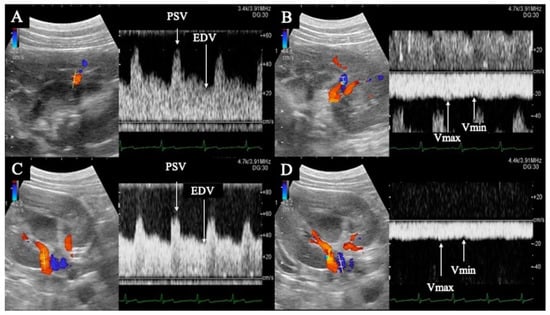

A diagnostic ultrasound system (ALIETTA70, Hitachi, Tokyo, Japan) was used for ultrasonographic guidance. After anesthesia induction, the dogs were kept in the right lateral recumbent position. Only the left kidney was delineated using a convex probe (C42, Hitachi, Tokyo, Japan), and color Doppler ultrasonography was used to delineate the interlobular artery and interlobular vein in horizontal sections, as well as the renal artery and renal vein in transverse sections. Pulsed Doppler ultrasonography (sample volume 1.0–6.0 mm, 8 MHz) was used to record the blood flow waveforms of the interlobular artery, interlobular vein, renal artery, and renal vein at the same location three times each (Figure 1). In all measurements, the Doppler angle of incidence was within 60°, and the correction angle was within 30°. Ultrasonography was performed at four time points: pre-administration and at administration of 2, 5, and 10 ng/kg/min doses.

PI, RI, peak systolic velocity (PSV), end diastolic velocity (EDV), and time average maximum velocity (TAMV) were determined from the interlobular and renal artery waveforms (Figure 1). The maximum (Vmax) and minimum (Vmin) venous flow velocities were measured from the blood flow waveforms of the interlobar and renal veins, respectively (Figure 1). The VII was calculated from the Vmax and Vmin of the interlobar and renal veins using the formula described below. The mean of all three measurements was used for statistical analysis. Each calculation was performed using the ultrasound system described previously.

Figure 1. Flow waveform of the renal interlobar artery (A) and vein (B), and renal artery (C) and vein (D). (A,B) are horizontal sections of the kidney; (C,D) are transverse sections. The renal interlobar artery (A) and renal artery (C) show pulsatile waveforms with peak systolic velocity in systole (PSV) and end diastolic velocity (EDV) in diastole. The renal interlobar vein (B) and renal vein (D) show flat, continuous waveforms; the maximum velocity is Vmax and the minimum velocity is Vmin.